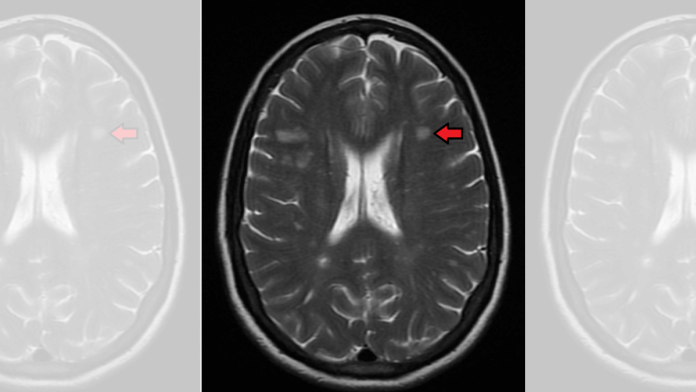

In MS, the immune system attacks the protective sheath of myelin that covers nerve fibres and causes communication gaps between the brain and the rest of the body. Eventually, the disease can cause permanent damage or deterioration of the nerve fibres.

However, the signs and symptoms of MS vary widely between patients and depend on the location and severity of nerve fibre damage in the central nervous system. Some people with severe MS may lose the ability to walk independently, see, or talk, drastically affecting their quality of life.